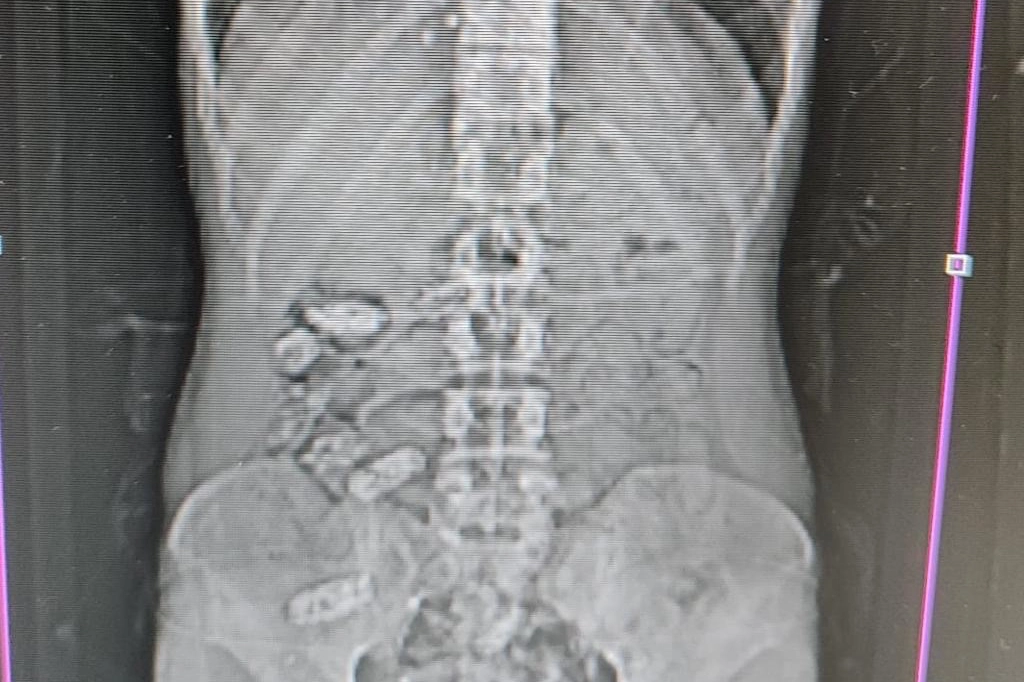

Gümüşhane’de polis ekiplerinin kontrol noktasında durdurduğu araç içerisindeki yabancı şahsın midesinden 18 adet kapsül halinde metamfetamin ele geçirildi. Edinilen bilgilere göre, Gümüşhane İl Emniyet Müdürlüğü’ne bağlı Narkotik Suçlarla Mücadele Şube Müdürlüğü ekipleri tarafından Akçakale Uygulama Noktası’nda durdurulan bir araç içerisindeki yabancı şahsın şüpheli hareketleri üzerine çalışma yapıldı. Uyuşturucu kuryesi olduğu ve yutma suretiyle uyuşturucu taşıdığından şüphelenilen şahsın Gümüşhane Devlet Hastanesi’nde yapılan kontrollerinde, midesinde 18 adet kapsül olduğu tespit edildi. Hastanede yapılan müdahalenin ardından şahsın midesinden çıkarılan kapsüllerin içerisinde toplamda 152,29 gram metamfetamin ele geçirildi. Hakkında Uyuşturucu Madde İmal ve Ticareti suçundan işlem başlatılan yabancı uyruklu şahıs yasal işlemlerinin tamamlanmasının ardından çıkarıldığı mahkemece tutuklanarak cezaevine gönderildi.